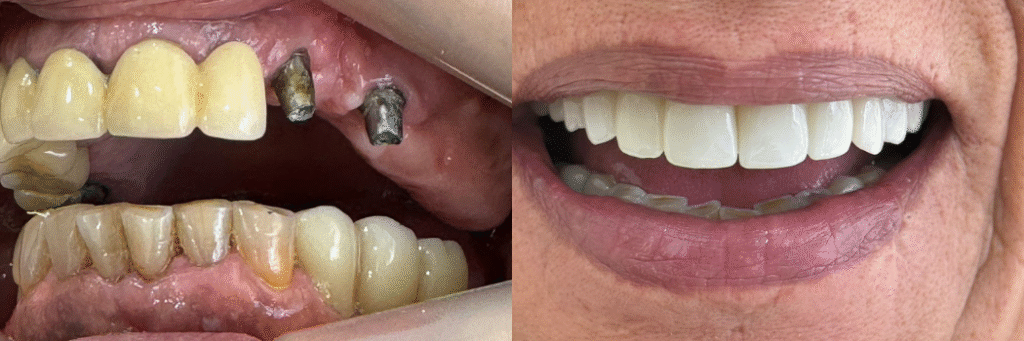

Rehabilitación integral sobre implantes